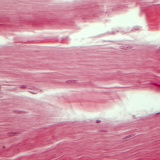

zumiranje: 400x

Biologija